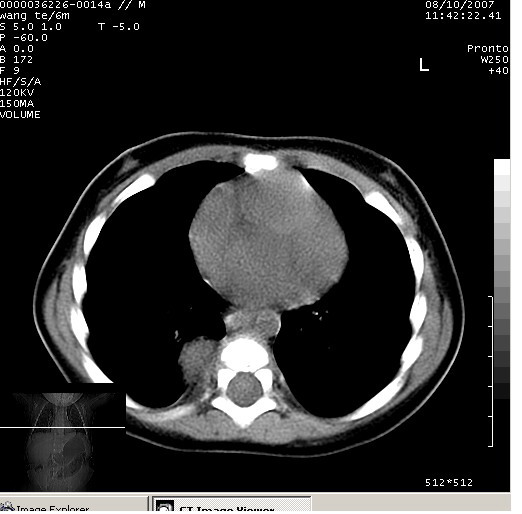

患儿男、6个月,因咳嗽三天曾拍胸片考虑肺部感染,这是在胸片后约一周左右作的ct。

右下肺纵隔旁软组织密度影,边界清楚,内见点状高密度影。支持考虑:神经源性肿瘤!

右下肺纵隔旁软组织密度影,宽基底紧贴胸椎与肋骨,边界清楚,内见点状高密度影。支持考虑:神经源性肿瘤!肺隔离症待排

右下肺纵隔旁软组织密度影,边界清楚,考虑神经源性肿瘤。

右下肺纵隔旁边界清楚软组织密度影,内见点状高密度影。考虑:神经源性肿瘤!

同意神经源性肿瘤的诊断,如果患儿一般情况不差的话,神经节细胞瘤可能性要大一些,隔离肺的可能性小,如果考虑叶内型隔离肺,孩子平时感染的机会可能比较多,增强后可排除

典型的神经源性肿瘤

支持神经源性肿瘤,有肋骨破坏。